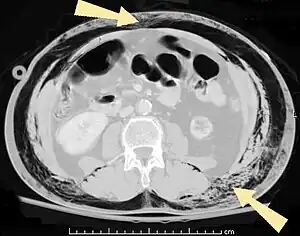

Abdominal

- Pneumoperitoneum (or peritoneal emphysema), air or gas in the abdominal cavity. The most common cause is a perforated abdominal viscus, generally a perforated peptic ulcer, although any part of the bowel may perforate from a benign ulcer, tumor or abdominal trauma.

- Pneumatosis intestinalis, air or gas cysts in the bowel wall

- Gastric pneumatosis (or gastric emphysema) is air or gas cysts in the stomach wall[6]